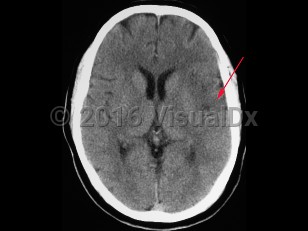

- Intracerebral hemorrhage – Bleeding directly into the brain parenchyma secondary to hypertension, trauma, bleeding disorders, aneurysm rupture, illicit drug use, or vascular malformations. Patients typically present with the gradual onset of symptoms over hours to days with headache, nausea, vomiting, and altered levels of consciousness. If the source of the hemorrhage is from the low-pressure side of the circulation, then the onset of symptoms is more likely to be gradual than if the source is from the high-pressure, arterial side, where symptoms can be quite abrupt in onset. Patients can also present with seizure.